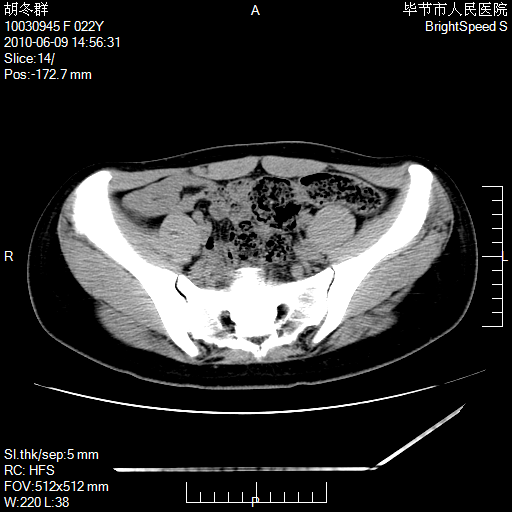

患者23岁,发现腹部包块3月。

我当时考虑重复膀胱,但我错得很厉害,我不明白,囊肿排尿后为什么能到膀胱位置。

囊性病变,可以增强检查,不除外输尿管囊肿

盆腔内囊性占位性病变;考虑左侧卵巢囊腺瘤。

有分隔、壁薄,支持考虑左侧卵巢囊腺瘤。

有分隔、壁薄,支持考虑左侧卵巢囊腺瘤。排尿后,膀胱缩小,由于重力作用,肿块下移就到了膀胱位置,很好理解。